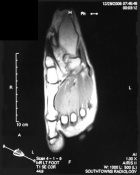

R.T. - 15 year old female noticed left dorsal foot mass two months ago; it is slightly tender to touch and bothers her with full plantar flexion, she also noticed some discoloration of the skin in the area

Zoom image: Radiological image Radiological image.